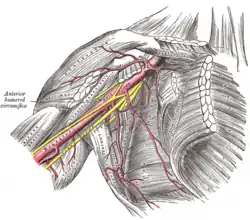

A artéria axilar e seus ramos.

A artéria axilar e seus ramos. -